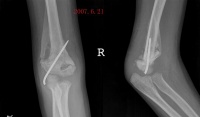

发热,局部皮温高,压痛,质硬肿块。局部肿块因逐渐骨化较前增大明显,肌肉僵硬萎缩,关节疼痛不明显,关节功能活动障碍。X线摄片示肿物周围花边状新骨大量生成,界限清楚,经过一段时间后,肿物停止发展并有所缩小,而形成较为致密的骨化性团块,可给予患肢依照早期手法按摩,然后术者一手持患肢肘关节近端,一手持患肢前臂中部。柔和稍用力逐渐被动屈伸肘关节,常常可听到骨化性肌炎断裂声,及粘连撕裂声此时肘关节的被动活动可达到基本正常范围。如遇骨性阻挡,切忌强行被动屈伸,以免再次发生骨折,应待骨化组织逐渐成熟及局限后。行手术治疗。手法治疗后,局部薰洗治疗,并指导病人在疼痛可耐受情况下,行肘关节以主动活动为主,被动活动为辅的功能锻炼。

3晚期(骨化期):

局部无疼痛,肌肉僵硬萎缩严重,关节强直在某一体位或仅有轻微的活动度,X线摄片示出现壳状骨性软骨骨化,范围局限骨化明显致密,行手术切除骨化组织及关节松解术,用肘外侧切口在肱骨外髁嵴部,分别向肘前及肘后剥离,显露骨化组织后将其切除并彻底松解粘连组织,闭合切口前应松止血带,仔细止血放置负压引流术后经3周制动进行关节主动活动,以免再发生粘连待刀口愈合拆线后行中药熏洗治疗。